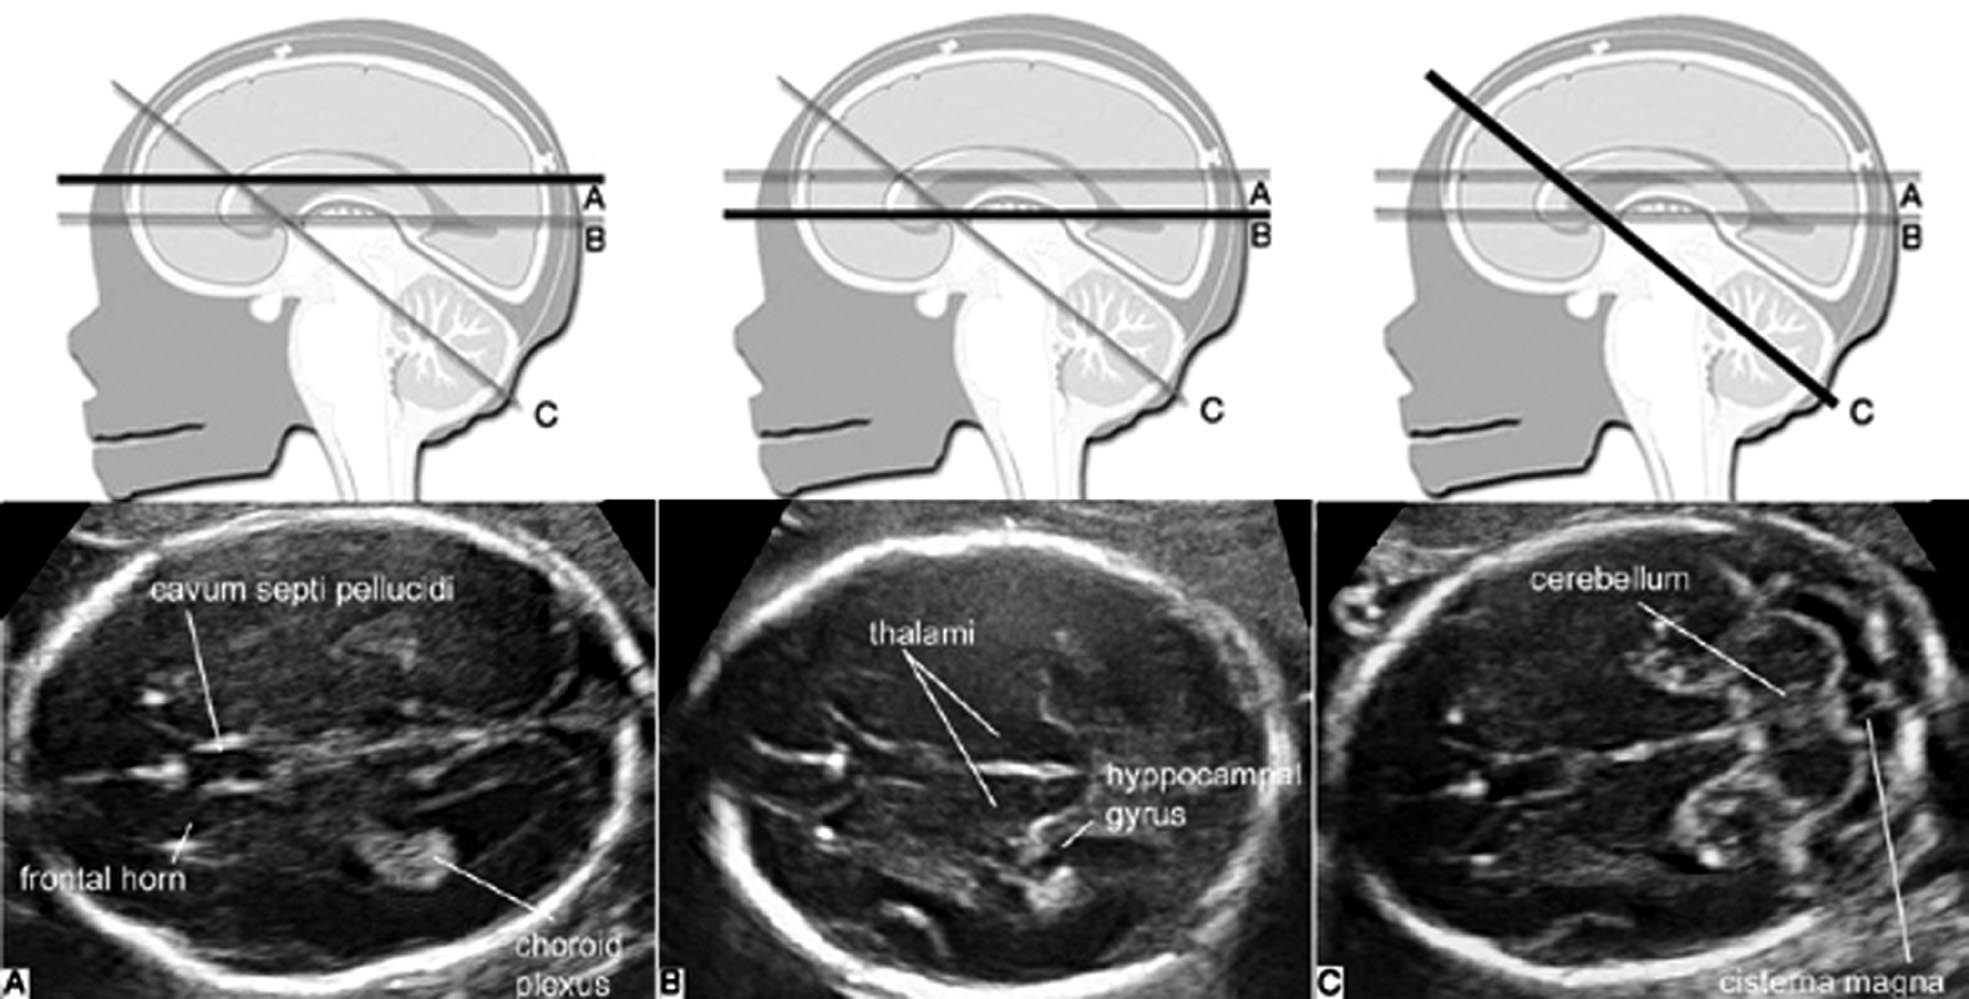

胎儿颅脑横切面最容易获得,系列的胎头横切面也是显示颅内结构的重要切面。常用的横切面主要有侧脑室水平横切面(TVP)、丘脑水平横切面(TTP)和小脑横切面(TCP)。

图7-1胎头横断面声像图

1.TVP 颅骨显示为环状椭园形强回声,回声对称。切面中显示的逗点状无回声为侧脑室(TV)前角和后角,后角内稍强回声的脉络丛(CP)近充满TV,形态规则,边缘清晰;中线回声的前部的无回声为透明隔腔(CSP),在妊娠晚期(TTP)或新生儿期CSP消失形成透明隔(SP)。PUE中CSP显示非常重要。一般在妊娠18~37周都可显示SP,<18周或>37周时可能不显示。CSP的显示与否有助于鉴别一些脑部畸形。

TVP还可显示中部两侧部分丘脑,脑中线可见。TV额角内侧壁几乎和大脑镰相平行,枕角向两侧分开离脑中线较远(图7-1A)。测量枕角与额角内径可判断有无脑室扩张,整个妊娠期间TV枕角内径均<10mm。STP由于CP呈强回声致其远侧大脑皮质回声低或极低,应注意和TV扩张或脑积水区别。

2. TTP 在TVP向下水平移动探头即可获得TTP,此平面是测量BPD的标准平面。颅骨呈椭圆形环状回声,对称,脑中线居中,中线回声的前1/3处的等号样回声为SP,SP之间的腔隙为CSP,正常时内径<10mm。由前向后可显示TV前角、对称的丘脑和海马回(图7-1B),小脑不显示;两侧丘脑之间的缝隙为第三脑室,正常时<2mm,向前经室间孔通向TV,向后经中脑导水管通向第四脑室。

3. TCP 获得TTP后声束略向尾侧旋转,即可获TCP。标准切面要求同时显示左右对称的小脑半球以及前方的CSP(图7-1C)。SP前外侧仍可显示TV前角,小脑与SP之间中线两侧的低回声为丘脑;小脑呈对称的半球形或蝶形回声,实质部分回声较低,随着妊娠的进展内部回声逐渐增强,但边缘回声增强更为明显;晚孕期小脑实质近边缘区域显示数条整齐的线状强回声为小脑裂。正常发育的小脑与孕龄有良好的关系。两侧小脑之间有回声较强、不均匀的小脑蚓部,后方与小脑相邻的无回声为小脑延髓池(CM)(图7-1C)。20孕周以前CM没有完全覆盖第四脑室,或可引起小脑或小脑蚓部畸形的假象,应当于20孕周以后予以确认。